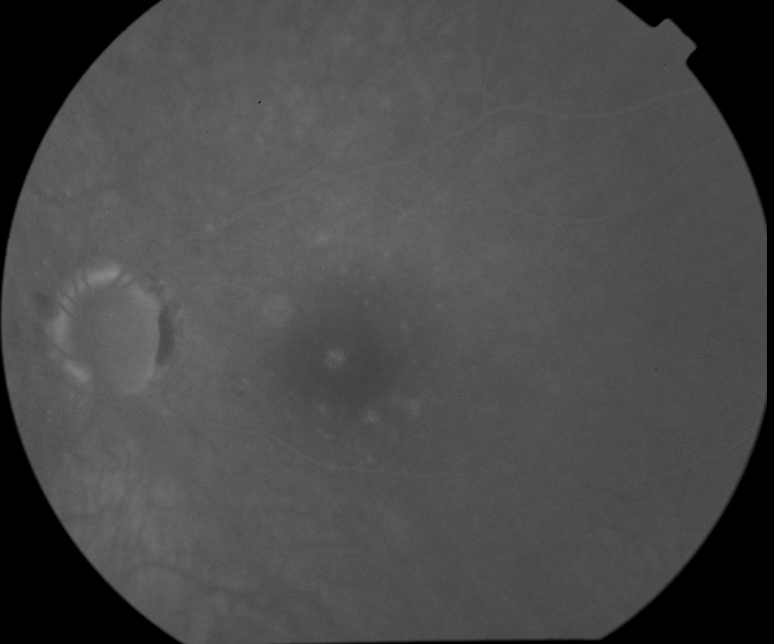

FUNDUS DESCRIPTION: |

OD OS |

OD Red-Free: Pre-Injection: Arterial: A-V: Venous: Recirculation: Late:

OS Red-Free: Venous: Recirc: Late:

Impression